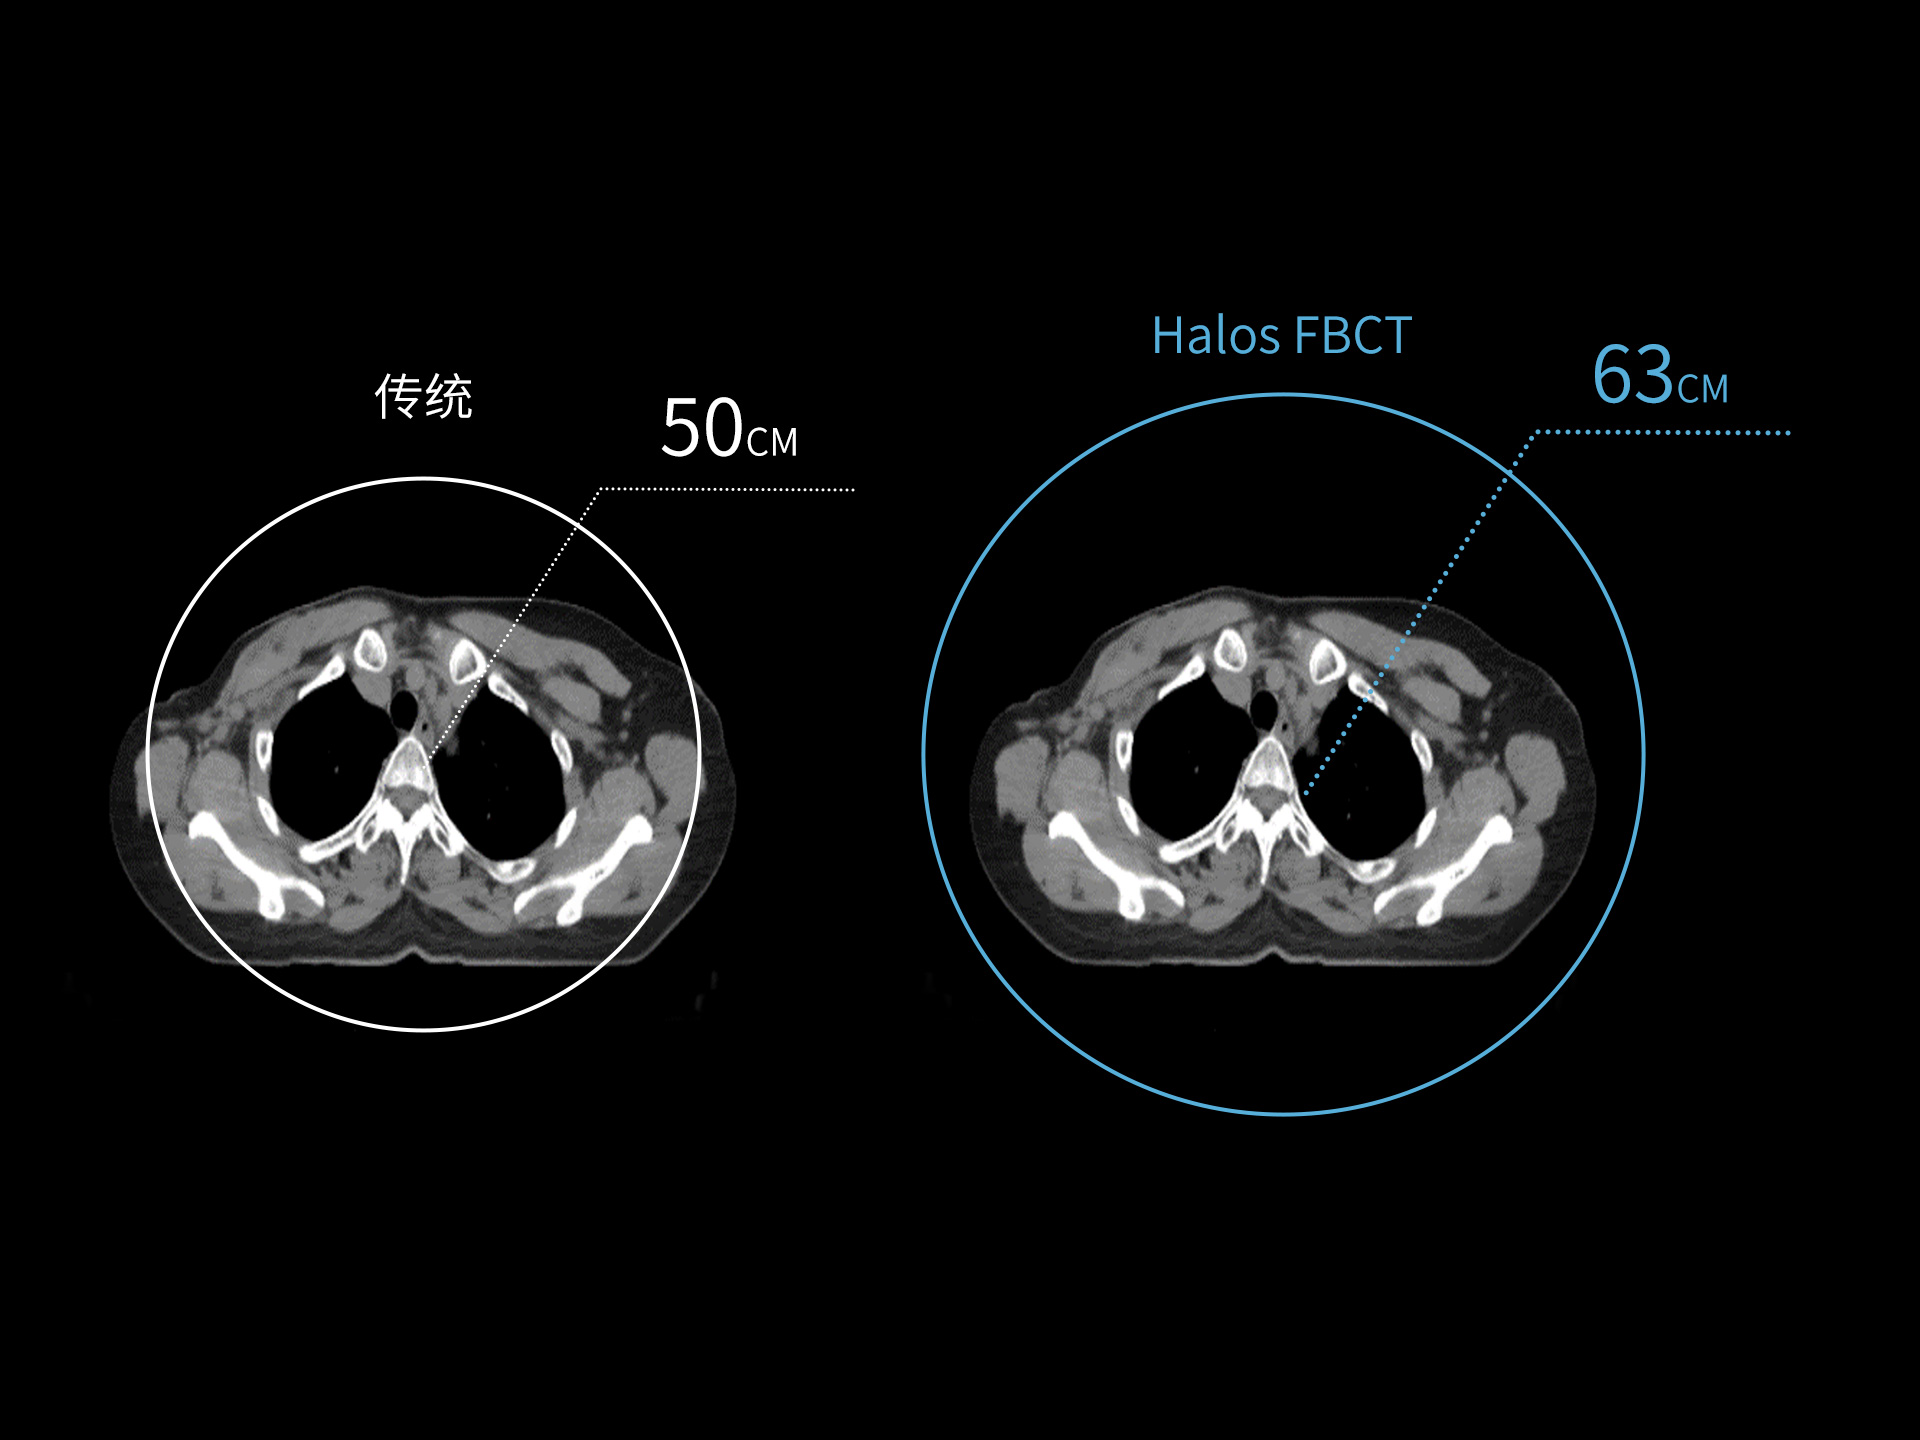

标准视野 63cm,避免扫描信息缺失

全景视野

87cm CT影像孔径设计适配多种摆位姿势,兼顾不同体型患者